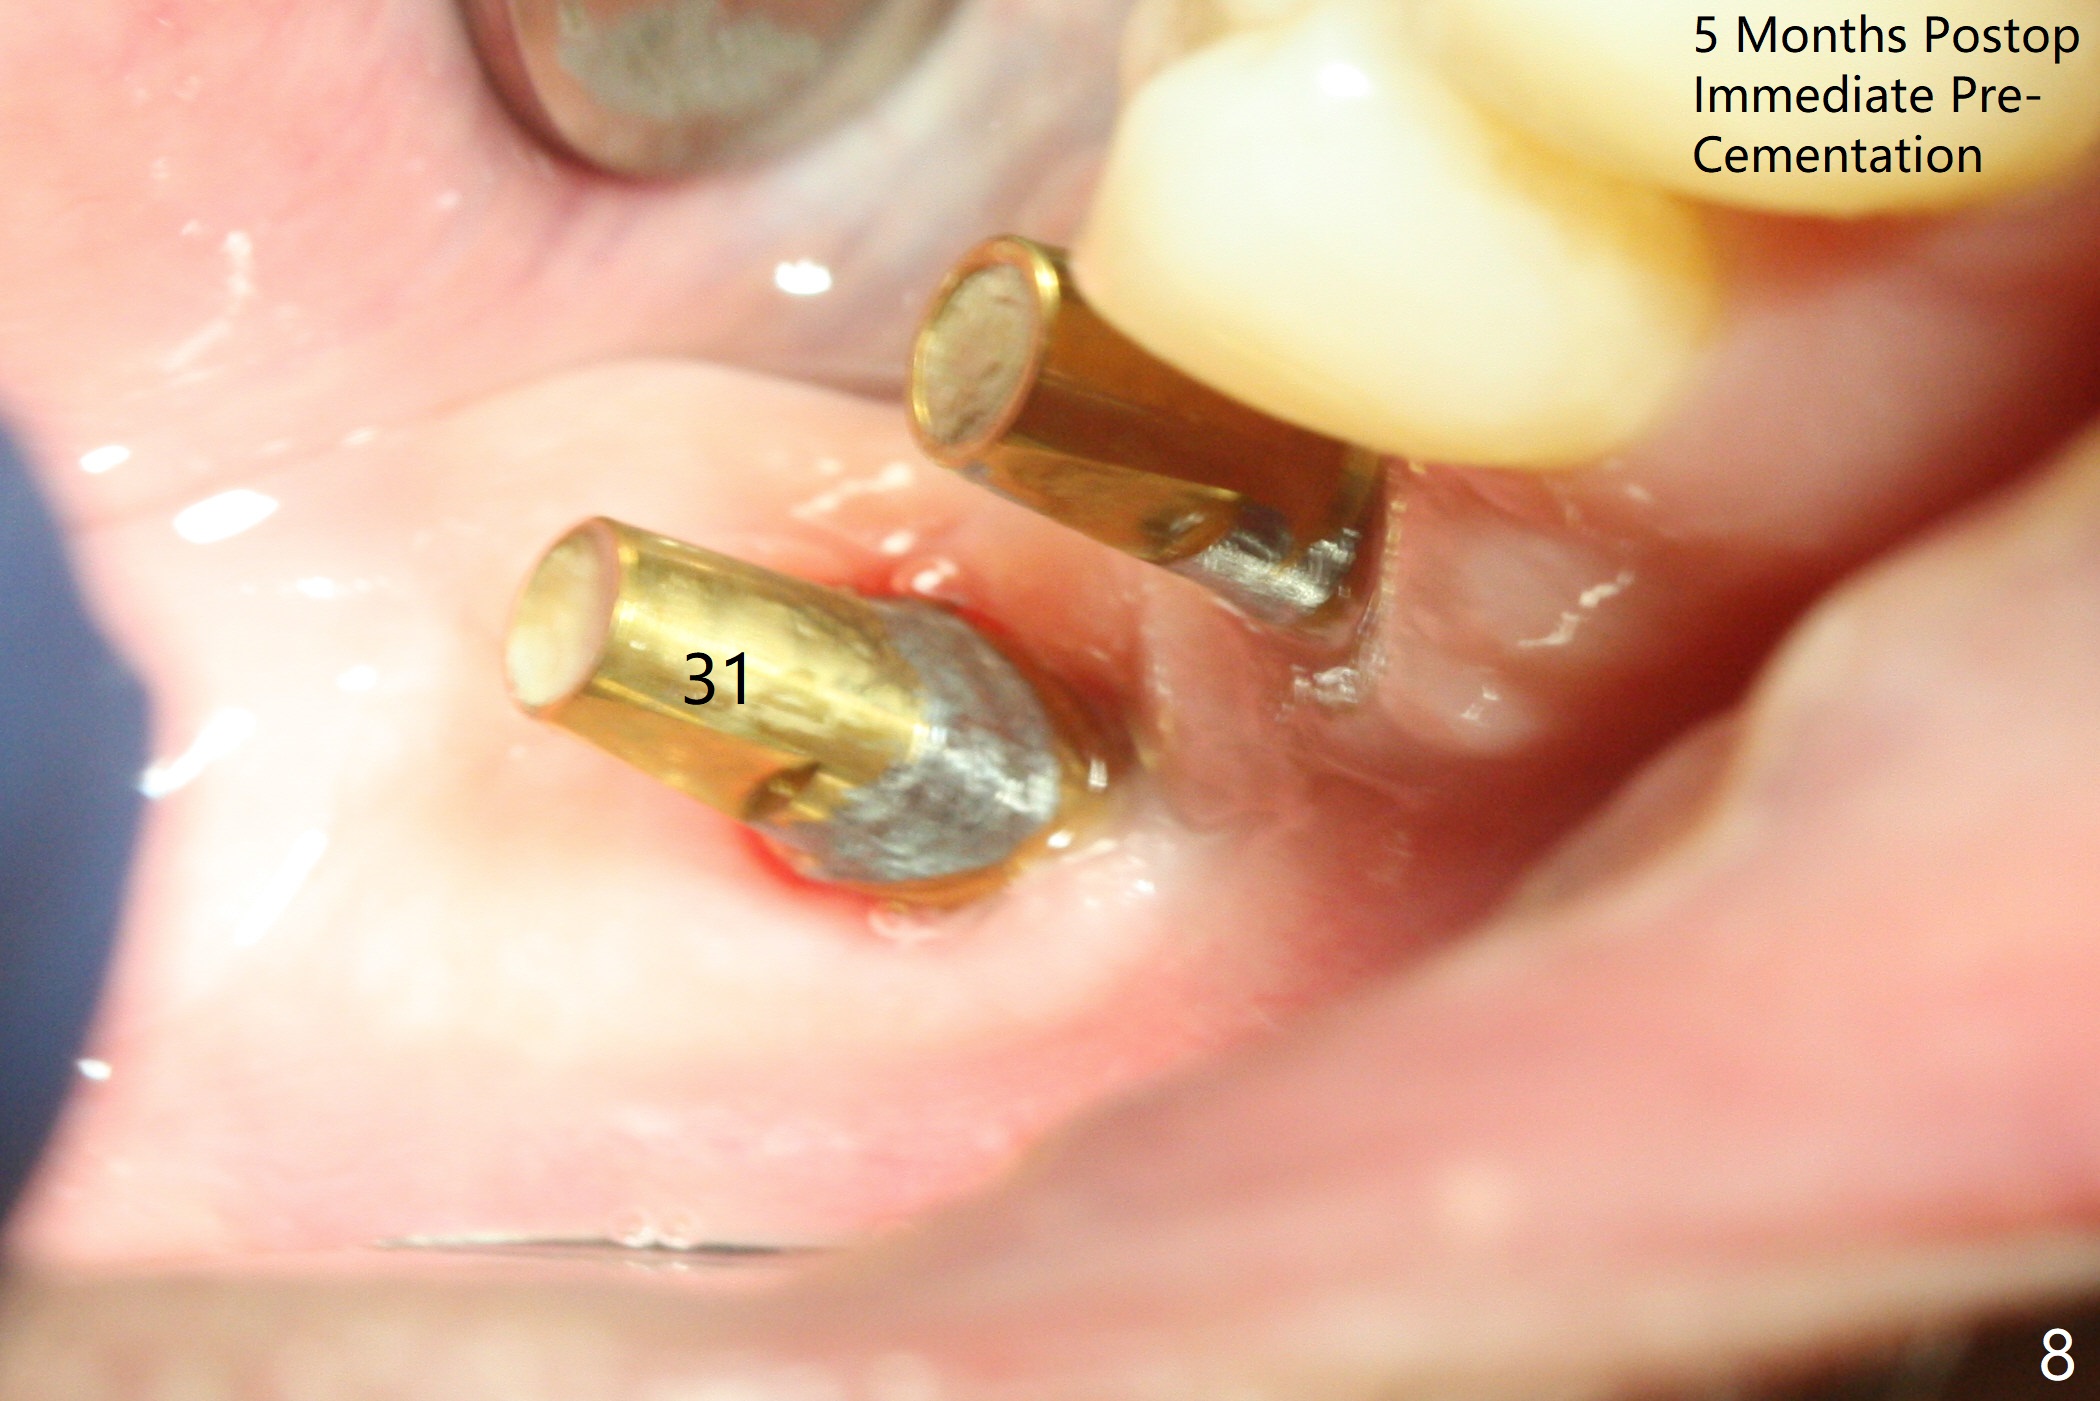

Osteotomy at the sites of #30 and 31 is initiated with Magic Split, followed by Magic Expanders (3.0 and 3.8 mm) at #31.  Initial depth of osteotomy is 13 mm with 2.2 mm drill (Fig.1).  After adjustment of the trajectory at #31 (Fig.1 arrow) and deepening the osteotomy by 2 mm, dummy implants are placed with stability (Fig.2).  Following increase in osteotomy at #31, the larger implant in fact loses stability (Fig.3).  The loose implant is pushed distal (Fig.4 arrow) with placement of autogenous bone mesial (*).  The stable implant at #30 (Fig.3) and its abutment (Fig.4) are used as a post to hold periodontal dressing, which covers the wound at #31 after placement of collagen plug and suturing.  In fact the same technique could be used when socket preservation was performed if an implant were placed at #30 at the same time.  When the periodontal dressing dislodges, the wound at #31 heals uneventfully (Fig.5,6).  The bone graft seems to remain in place 3 months postop (Fig.7).  The implant is uncovered with placement of a 6.8x7 mm healing abutment 4 months postop.  When a cementation abutment is placed and prepped, the buccal margin is much lower than the lingual (Fig.8 taken prior to cementation).  The patient enjoys mastication with the new implant crowns 3.5 months post cementation (Fig.9).